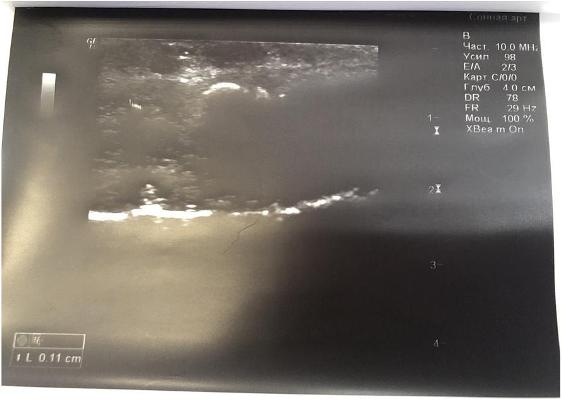

В глубине кавернозного тела определяется одиночная гиперэхогенная тень (фиброзная бляшка) размером до 0,11см дающая чёткую эхо-тень в виде акустической дорожки.